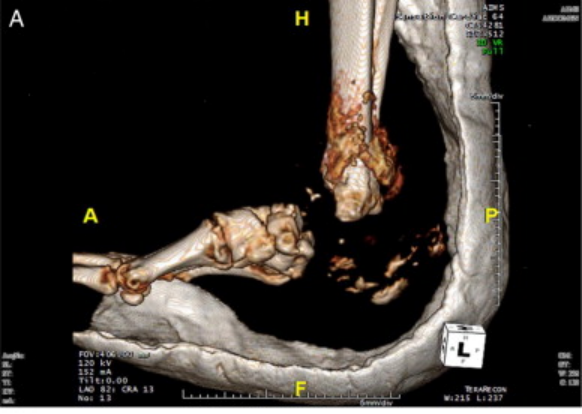

严重的Charcot足,后足骨几乎完全溶解消失